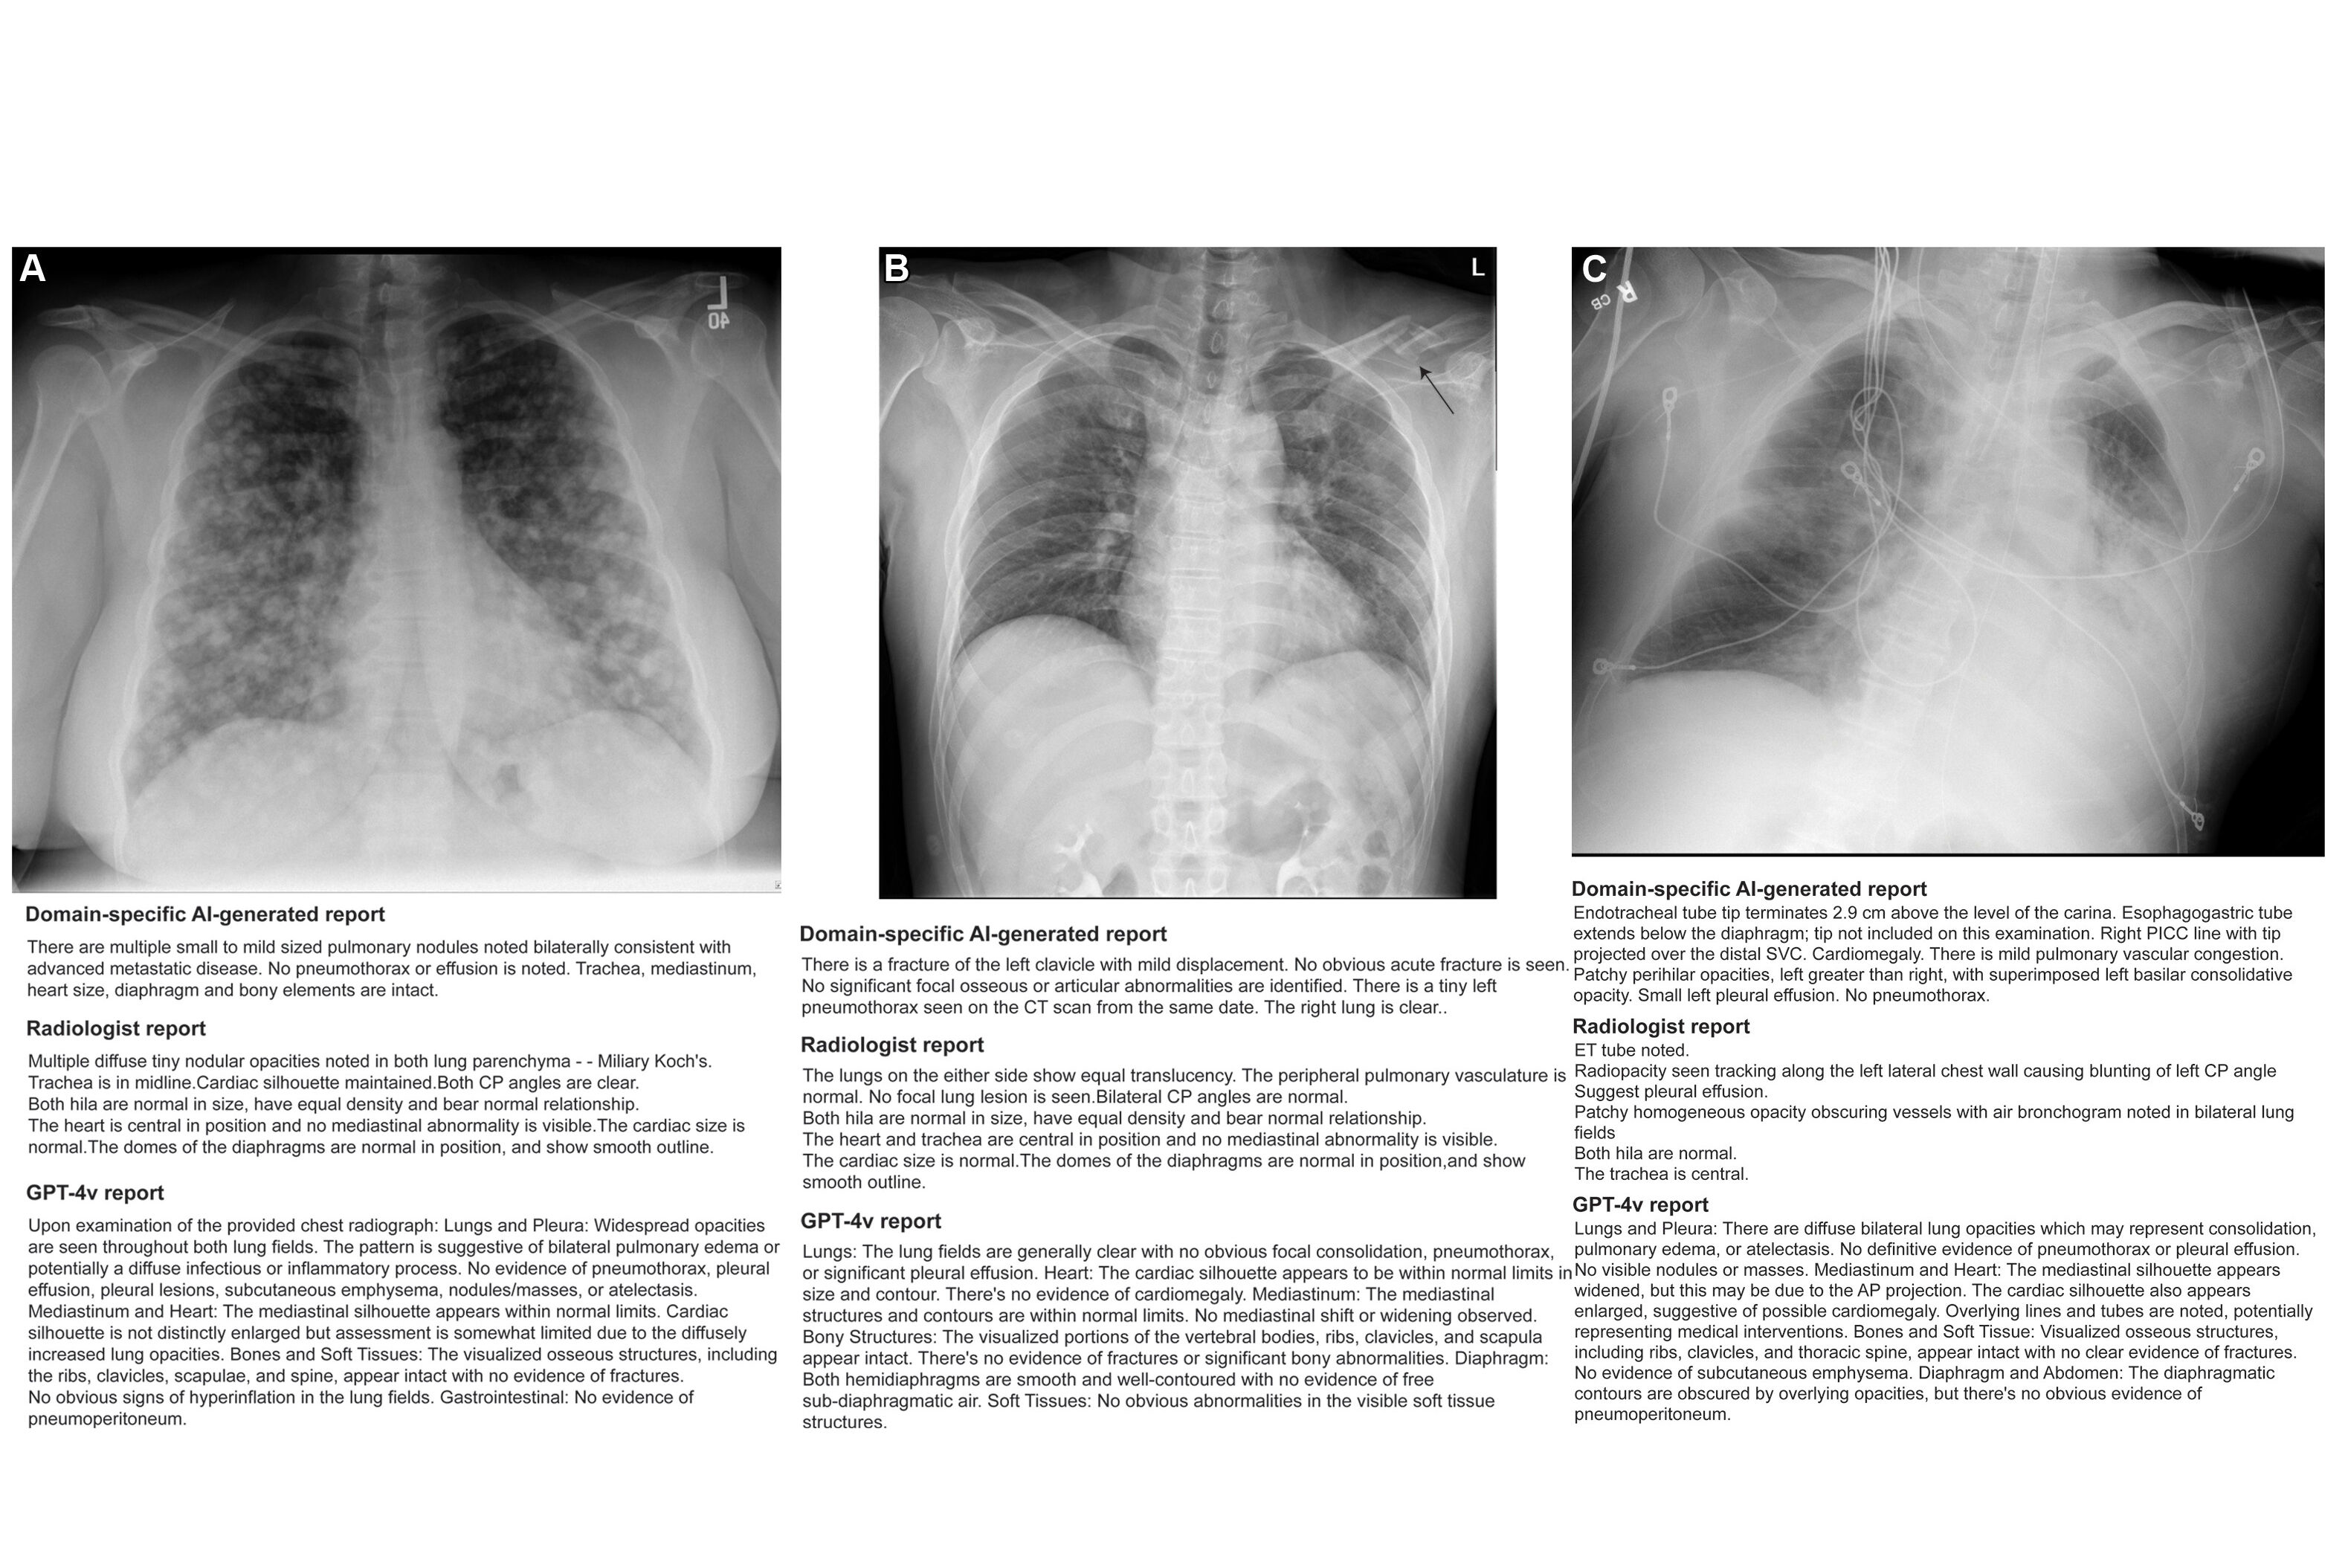

Saliency maps using Grad-CAM++ (E and H) show the model’s point of interest in chest radiographs (C and F) of patients with achalasia. The model’s point of interest is highlighted with red, yellow, and green. In both the upper and lower panels (E and H), the point of interest is located in a region around the upper esophagus that corresponds to an air esophagogram and/or air-fluid level in the esophagus in the barium esophagogram (D and G). Osaka Metropolitan University. Image available for republishing under Creative Commons license (CC BY-NC-ND 4.0)